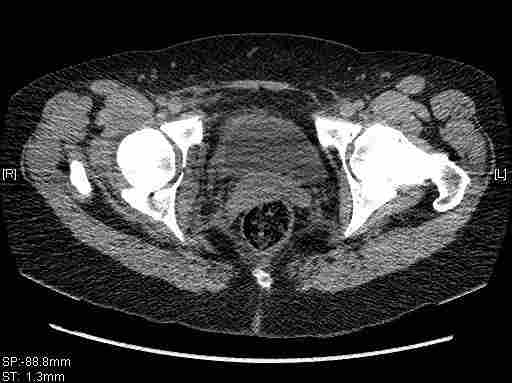

[Ortho] [2/2] Re: Т-образный перелом вертлужной впадины

Остальные срезы.